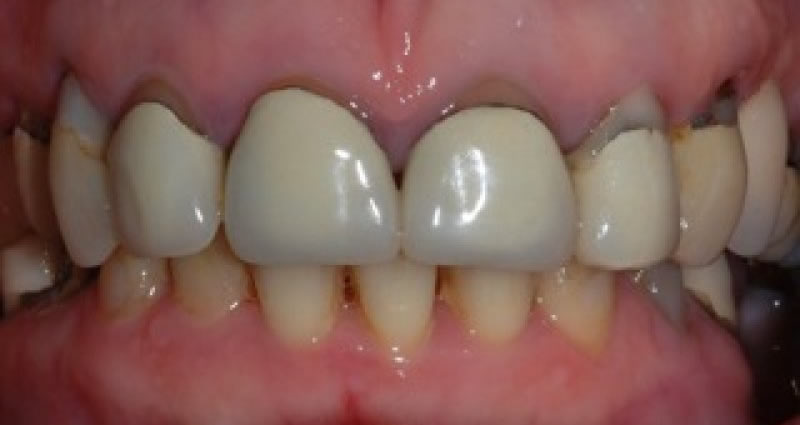

Upper crowns and lower composites (4 images)